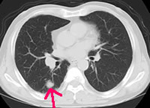

胸部CT

陰になっている部分や小さい病変もよくわかります。

| 胸部CT | 12,100円 | 咳・痰・胸痛など | 肺癌・肺炎・肺気腫など |